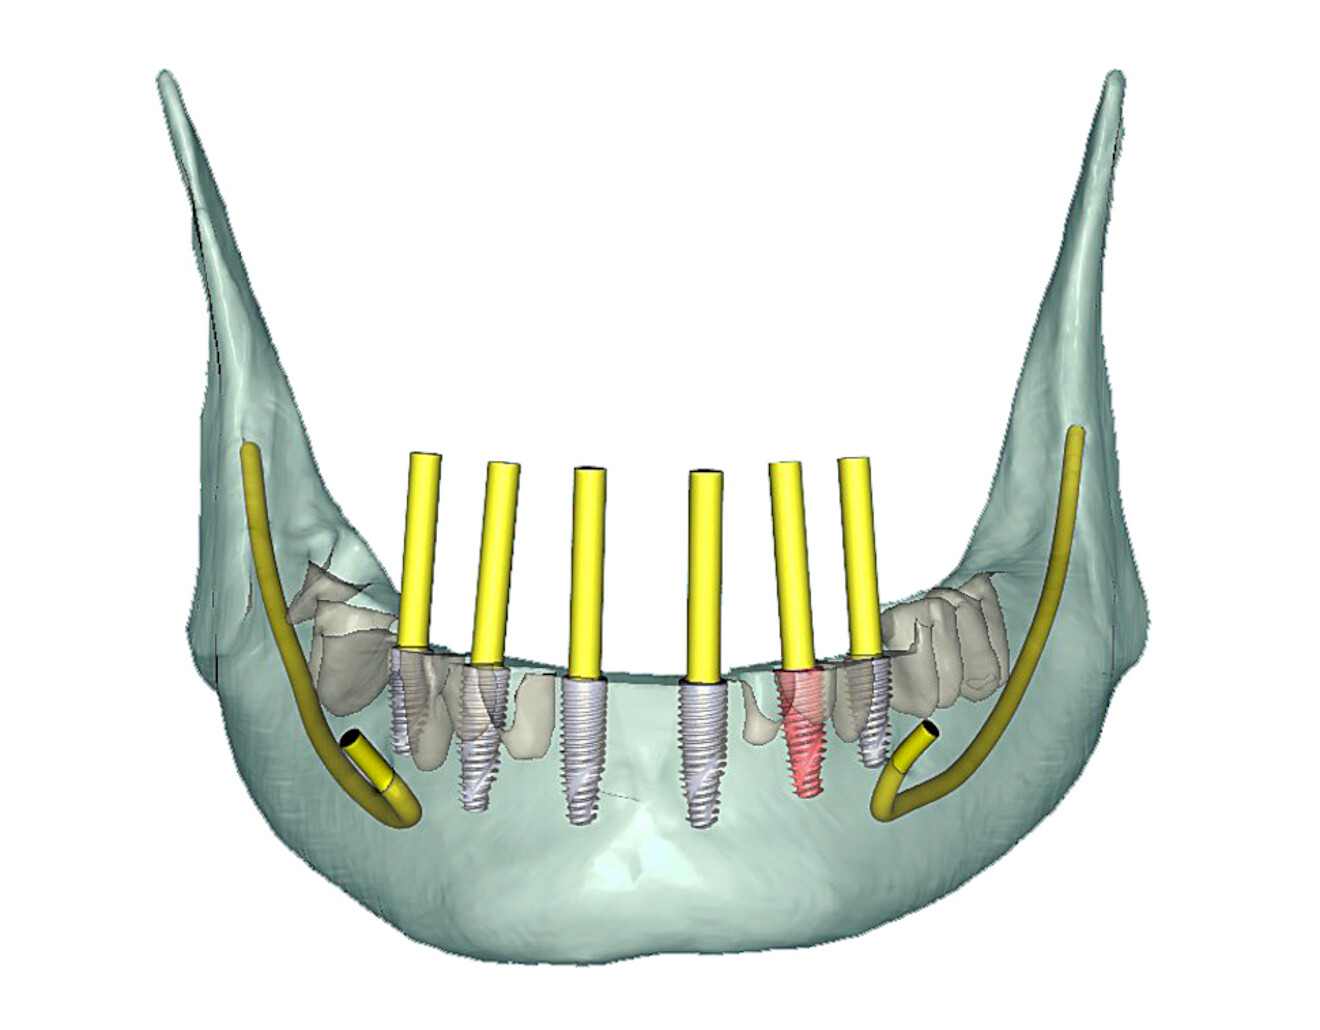

The mandibular arch followed a similar surgical protocol utilising a bone-borne surgical guide after tooth extraction and bone reduction. The advanced bone and tooth segmentation illustrated the severe bone loss almost to the apex of many of the mandibular roots (Fig. 13a). Using selective transparency, the roots and bone could be closely evaluated (Fig. 13b). 3D volumetric reconstruction simulating the post-extraction bone helped provide a unique view of the mandibular bony anatomy (Fig. 14a) and aided in finalising the location of each implant (Fig. 14b).

Fig. 13a: Fully segmented mandibular bone and teeth.

Fig. 13b: Selective transparency view visualising the roots, bilateral mental nerves and inferior alveolar nerve (yellow arrows point to the apices of the roots, showing the extent of the bone loss).